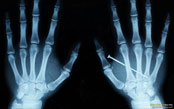

It was a dark night in 1895, a guy named Wilhelm asked his wife, Bertha, to place her hand on a photographic plate while he directed rays at it for fifteen minutes. She was taken back and somewhat frightened by the first X-Ray plate of a human hand! She felt like it was a premonition of death. Unfortunately, due to what we feel was probably over exposure to radiation (nothing slips by us!) they both died of cancer.